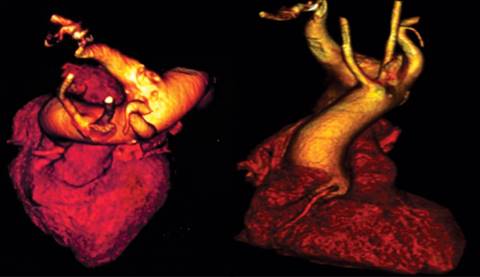

Se realizó una TAC contrastada, con la cual se observó una variante anatómica: origen aberrante de la subclavia derecha. Se obtuvo calcio coronario en 130 UA. Se llevó a cabo una aortografía, que reveló un origen único de ambas carótidas, origen independiente de la subclavia izquierda y sobre la aorta torácica descendente, un trayecto ectásico hacia la subclavia derecha, lo que confirmó la presencia del divertículo de Kommerell. La coronariografía dejó ver enfermedad arterial coronaria severa de un vaso, con oclusión de 30% del tronco coronario izquierdo, lesión ateromatosa de la DA con oclusión proximal de 90% y media de 100%, compatible con oclusión crónica total, lo que condicionaba cardiopatía isquémica crónica (Figuras 2 a 5).

Figura 4: Tomografía contrastada donde se aprecia la salida aberrante de la arteria subclavia derecha.

Figura 5: Aortografía: se muestra la presencia del divertículo de Kommerell en el origen de la arteria subclavia derecha aberrante.